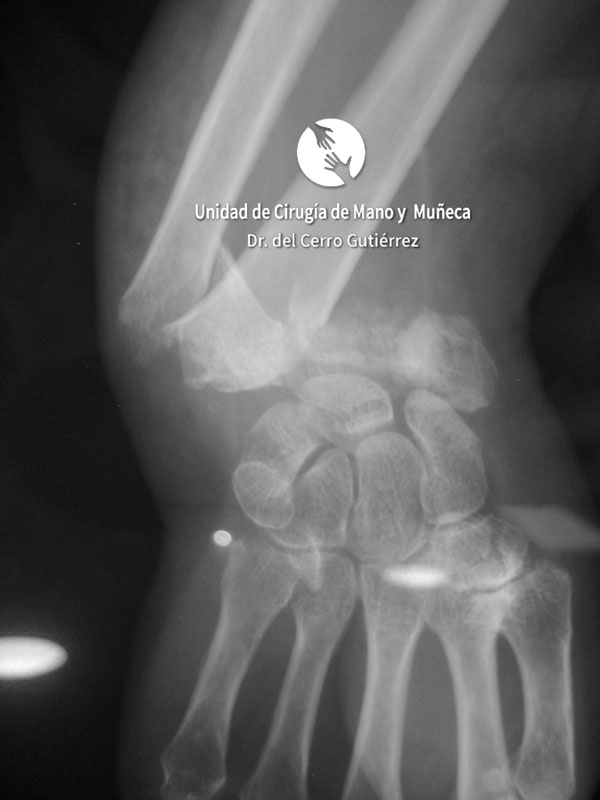

Imágenes de diagnótico de fracturas del radio distal de la muñeca

Fractura del Radio. Avulsión Estiloides.

Fractura del Radio. Desplazamiento Dorsal.

Fractura del Radio. Fractura Extraarticular

Fractura del Radio.

Fractura del Radio. Fractura del Escafoides.

Fractura del Radio. Conminuta y Articular.